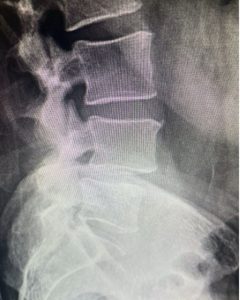

Image 1: This patient had spinal stenosis at L4-5 on MRI that looks straightforward as the first image shows.